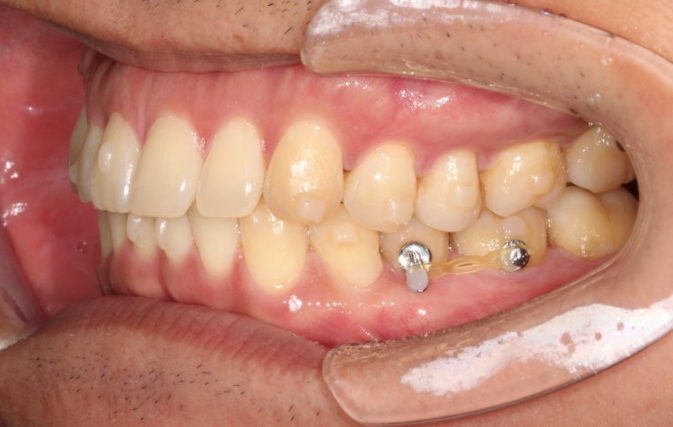

아래 작은어금니의 완벽한 회전을 위해서 고무를 걸 부가장치를 붙인채 치료를 진행했습니다.

가위교합의 빠른 해결을 위한 입천장의 교정용 나사도 썼습니다.

안으로 쓰러져 있던 큰어금니도 잘 세워졌고 가위교합도 해소가 되었습니다.